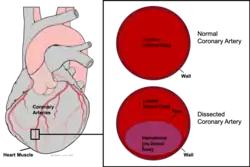

| Coronary artery dissection involves the formation of a hematoma (purple) within the walls of the coronary artery. | |

Spontaneous coronary artery dissection (SCAD) is an uncommon but potentially lethal condition in which one of the coronary arteries that supply the heart, spontaneously develops a blood collection, or hematoma, within the artery wall due to a tear in the wall. SCAD is one of the arterial dissections that can occur.[1]

SCAD symptoms are the result of a restriction in the size of the lumen of the affected coronary artery. A bleed within the wall of the artery (tunica intima) originating from the microvessels that perfuse this muscular layer (vasa vasorum) leads to a collection of blood, or hematoma, between the layers of the artery wall.[1] The hematoma pushes close the lumen, preventing blood from flowing to the heart muscle (myocardium). In some cases (~30%) this hematoma (also referred to as an intramural hematoma) is also accompanied by a tear in the inner most layer of the artery - a monolayer of endothelial cells called the tunica intima. It is not clear if this precedes or follows a bleed within the wall of the artery.[9] The tracking of blood within the artery wall (both in the presence or absence of an intimal tear) is referred to as a "false lumen".[10][11][12] The restriction of blood flow in the 'true' lumen limits the availability of oxygen and nutrients to the heart muscle, or myocardium. As a result, the myocardium continues to demand oxygen but is not adequately supplied by the coronary artery. This imbalance leads to ischemia, damage, and in some cases can lead to death of the myocardium tissue, causing a heart attack (myocardial infarction).